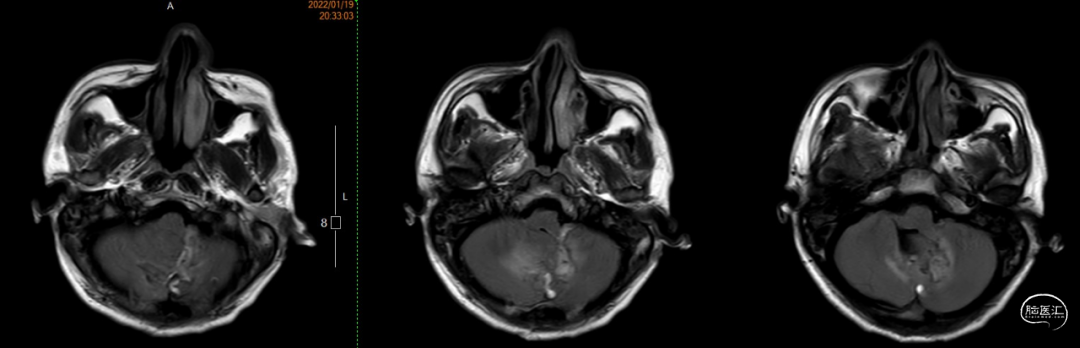

术前MRI:T2显示瘤周大量流空信号影,Flair显示左侧瘤周水肿边界欠清。

T1增强显示肿瘤血供非常丰富,有粗大引流静脉向窦汇及直窦引流。